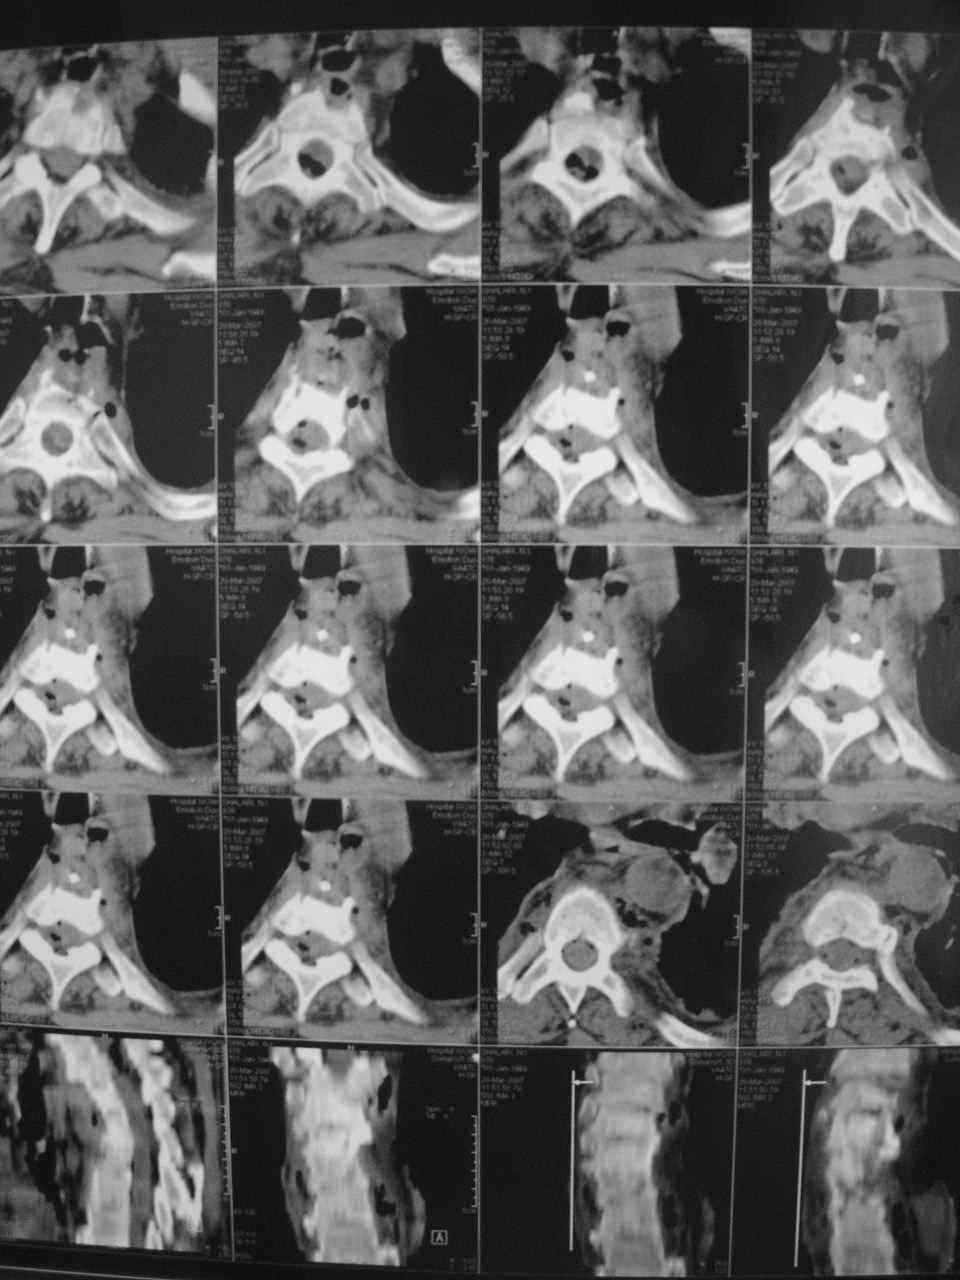

1. Rо-графия грудного и поясничного отделов позвоночника - деструкция с клиновидной деформацией Th5-6. Закл.: застарелый компрессионный перелом? Мт? 2. УЗИ внутренних органов - внутренние органы без патологии. Простата визуализируется с трудом. Края неровные, размеры 6,2х4,8х5,3 см., структура неоднородная. Объем мочевого пузыря - 600,0 мл. Заключение : Хр. б\к холецистит, Аденома простаты. Сч простаты? 3. ФГДС - заключение: Эрозивный дуоденит. Атрофический гастрит. 4. Рентгенография легких - без патологии. 5. Ретроспективный пересмотр флюорограмм за последние 3 года - без патологии. Повторно выполнены клинические и биохимические анализы крови. Заслуживает внимания только нарастание лейкоцитоза (L - 14,0П-4,С-68,Л-64,М-5, СОЭ - 65 мм.\ч). Ликвор: цвет - светло-желтый, ксантохромия- наблюдается, прозрачность - мутная, нейтрофилы - 95%, лимфоциты - 5%, цитоз - 588х106/л, белок - 9,9 промилей. В осадке - I пробирка: L- в большом количестве, Э- неизмененные, в большом количестве,Э- измененные, 1-3 в п\з. II пробирка: L - в небольшом к-ве, Э - неизмененные, 7-10 в п\з, Э- измененные, 2-3 в п\з. К ранее назначенному лечению добавлены инфузионная терапия, антибиотики ( цефтриаксон, ципринол), гормональная терапия (дексаметазон 8,0 мгх2 р\д), гепарин, диуретики, посиндромная терапия. Осмотрен урологом, онкологом. Достоверных данных за наличие Мт. не установлено. В связи с неясностью диагноза, был направлен на КТ в Тираспольскую РКБ. 21 марта больной скончался. На вскрытии - внутренние органы без признаков какой-либо патологии. При разведении волокон передней продольной связки в проекции Th4-6 была вскрыта гнойная полость с наличием деструкции тел указанных позвонков, с прорывом гнойника в позвоночный канал. Дуги и отростки позвонков - без признаков поражения. Гной сливкообразной консистенции, зеленоватого цвета. Гнойных затеков в мягких тканях также не обнаружено.Таким образом, выставлен п\а диагноз: гнойный остеомиелит тел Th4-6 c прорывом в позвоночный канал.

Насчет лечения - вполне адекватная консервативная терапия. Возможно было дополнить введение постоянного эпидурального катетера с введением антибиотиков и дренированием гноя(еще вариант - введение двух эпидуральных катетеров на разных уровнях, положение пациента на кровати с приподнятым головным концом, введение антибиотиков только в верхний. своеобразный "лаваж" позвоночного канала). Идеалом, конечно, была бы санация очага. На представленной КТ не совсем видно дату(сделана уже в период обострения?). На КТ можно заподозрить гнойную природу очага по плотности, характеру распространения. После удаления очага возможны множество вариантов выполнения дефектов.

КТ от 20 марта 2007 г. В приложении - описание КТ.

На КТ можно заподозрить

> гнойную природу очага по плотности, характеру распространения.

Обратите внимание, радиолог Тираспольской РКБ тоже подозревает остеомиелит. При этом, рекомендует консультацию фтизиатра.